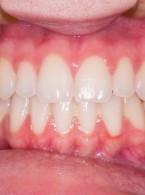

Chirurgiczne wycięcie zlokalizowanego przerostu dziąseł za pomocą lasera: opis przypadku